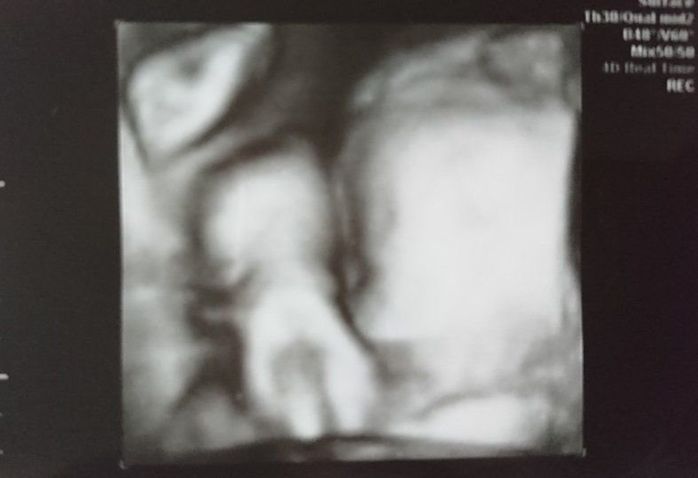

妊娠33週目のエコー写真

やっと産休に入り、体を休める事ができた幸せな時期でした。時間に余裕ができたので、少しずつ男の子の名前を考えていました。予定の帝王切開の手術まで1カ月あるので、まだ出産の準備はしていませんでした。まさか次の妊婦健診の日に産む事になるとは、夢にも思っていませんでした。赤ちゃんの推定体重は2493gでした。